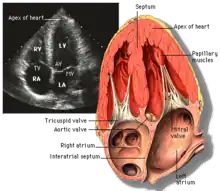

Transthoracic echocardiography (TTE) uses ultrasonic waves for continuous heart chamber and blood movement visualization. It is the most commonly used imaging tool for diagnosing heart problems, as it allows non-invasive visualization of the heart and the blood flow through the heart, using a technique known as Doppler.